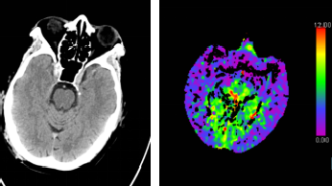

腦部CT檢查即電子計算機斷層掃描(Computed Tomography),是一種無創(chuàng)性檢查方法,通過X線和計算機技術(shù)相結(jié)合,獲取腦部結(jié)構(gòu)的橫斷面圖像,這種檢查方法可以清晰地顯示顱內(nèi)結(jié)構(gòu),對于診斷腦出血、腦梗塞、腦腫瘤等疾病具有重要意義。

2、局限性:雖然腦部CT檢查具有較高的診斷價值,但也存在一定的局限性,對于某些疾病,如早期腦梗塞、輕微腦震蕩等,CT檢查可能無法準(zhǔn)確診斷,腦部CT檢查主要關(guān)注結(jié)構(gòu)異常,對于某些功能性問題,如認(rèn)知障礙、情緒問題等,無法直接判斷。

2、其他檢查方法:除了腦部CT檢查外,還有其他檢查方法,如腦電圖(EEG)、磁共振成像(MRI)等,可以輔助診斷腦部疾病,這些檢查方法可以檢測腦部功能異常和某些細(xì)微結(jié)構(gòu)變化。